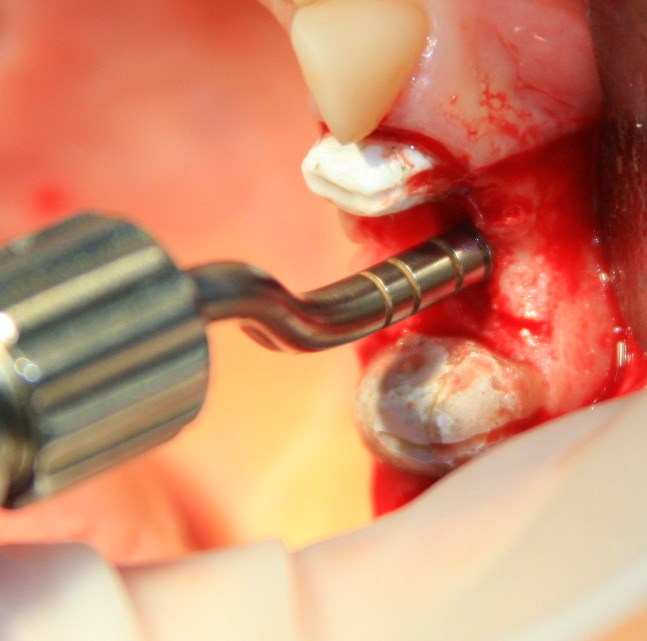

Закрытый (вертикальный) синуслифтинг производится через уже подготовленную лунку импланта с помощью специальных инструментов — остеотомов-остеоконденсоров (рис 6).

Существующий «баллонный» синуслифтинг также является закрытым. Как следует из названия, при проведении вертикального синуслифтинга отсутствует контроль над состоянием слизистой оболочки гайморовой пазухи, поскольку увидеть ее через лунку импланта диаметром, к примеру, 3,4 мм без специального оборудования нельзя (рис 7, 8).

Рисунок 7, 8. Проведение закрытого синуслифтинга с помощью остеотомов-остеоконденсоров.